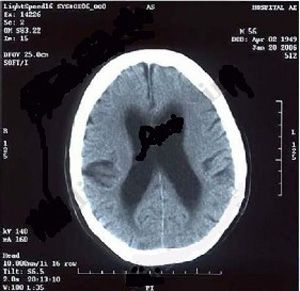

正常脑积水ct图片

正常脑积水ct图片,脑积水磁共振图片

2010年2月10日ct显示轻度脑积水以及脑内旁多灶低密度区

【医疗科普】拍ct意外查出脑积水,没有症状还要治疗吗

脑积水ct显示,侧脑室明显扩大,脑沟脑回消失

脑积水ct图片怎么看

脑积水ct表现图

脑积水ct图解

脑积水ct图片